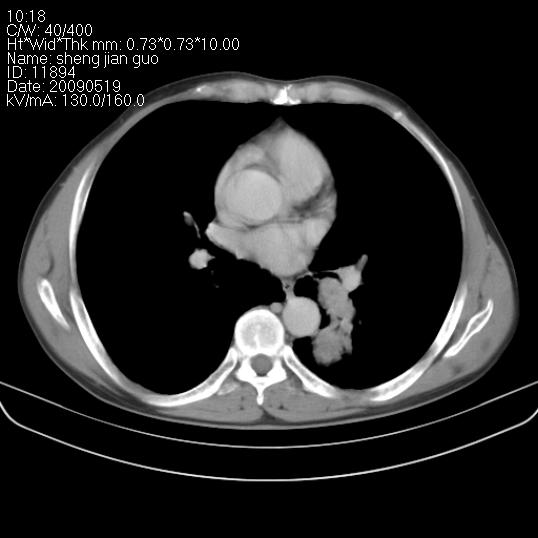

以下是引用zjzjr在2009-5-19 17:25:00的发言:[br]支持楼主考虑,另左肺下叶阻塞性炎症。

以下是引用zhao_bin2008在2009-5-19 17:48:00的发言:[br]支持左肺下叶周围型肺癌并阻塞性肺炎。

以下是引用zsl6918在2009-5-20 7:10:00的发言:[br]左侧中心型肺癌!